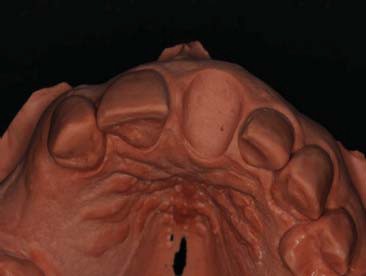

Foi realizado uma moldagem prévia a cirurgia, e no modelo de trabalho, foi realizado um desgaste com brocas carbide esféricas seguindo o limite da margem gengival com aproximadamente 2 mm de profundidade. A concavidade foi isolada e preenchida com resina flow (Z350, 3M®) até o nível da marcação cervical, respeitando uma área central mais palatina para acilitar a posterior união com o cilindro provisório. Em seguida, realizam-se o acabamento, o polimento e a desinfecção da peça, deixando-a pronta para o uso cirúrgico (figura 3, figura 4, figura 5 e figura 6).